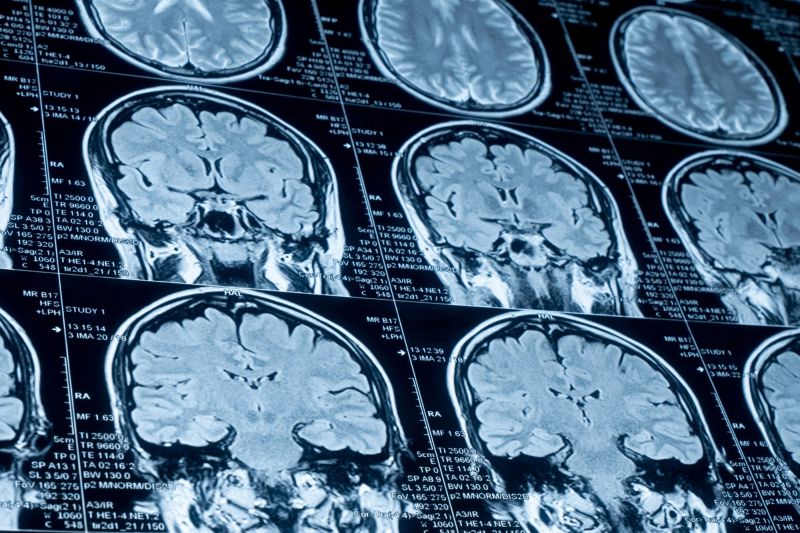

• MR (magnetne rezonance) može omogućiti radiologu i neurohirurgu da pregledaju krvne sudove sa preciznim pregledima.

CT ili MR skeniranje mozga može se koristiti da se utvrdi da li se moždani udar već dogodio.